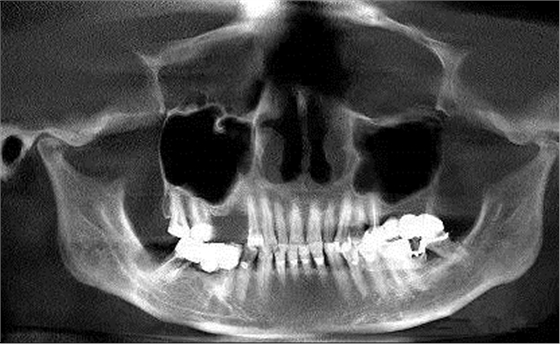

第四圖:上頜竇發(fā)育不足,上頜竇底骨高度充裕,通常頰側(cè)骨壁超級厚,看下圖2.臨床上種植常不需要提升措施。(如需提升,切記頰側(cè)骨厚度過大,開窗的困難性劇增)